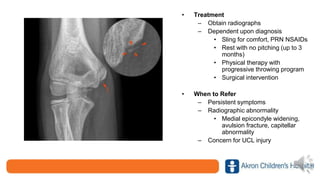

Little League Elbow

• Treatment

– Obtain radiographs

– Dependent upon diagnosis

• Sling for comfort, PRN NSAIDs

• Rest with no pitching (up to 3

months)

• Physical therapy with

progressive throwing program

• Surgical intervention

• When to Refer

– Persistent symptoms

– Radiographic abnormality

• Medial epicondyle widening,

avulsion fracture, capitellar

abnormality

– Concern for UCL injury